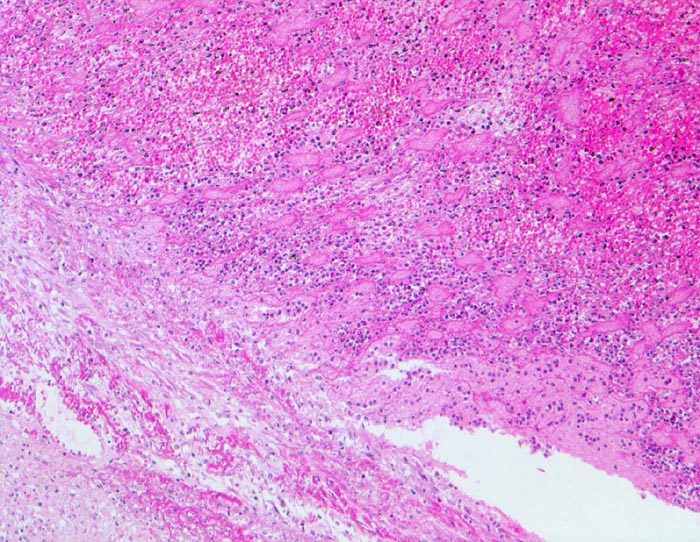

Parietalthrombose über Myokardinfarkt

Über dem Infarkt, dem Endokard aufgelagerter geschichteter Korallenstockthrombus bestehend aus Fibrin, Granulozyten und Erythrozyten.

Diagnose eines Myokardinfarktes vor 4 Tagen.

Histologie

50